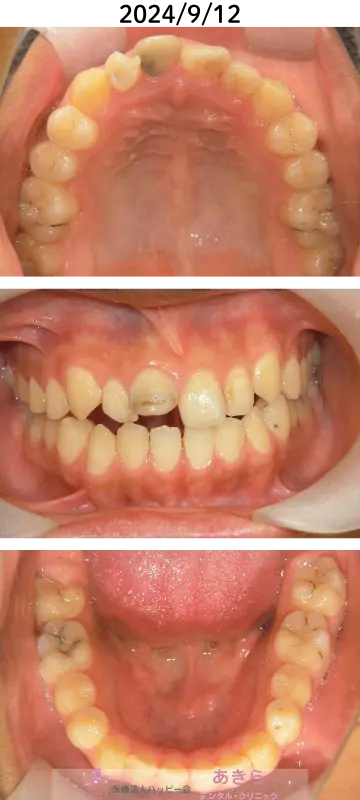

2024年9月12日 口腔内(経過)

経過

- 2021年7月より「SHA=SH装置」SH療法スタート。

- 歯列が直立してくることにより、早期接触がおこるため、随時必要枠での咬合調整が必要になります。

- SHA修理1回

- 前歯部にパワーチェーンによる右上2番矮小歯の捻転改善を促しました。

- 2024年9月に保定

- 2024年同9月に「右上1番・2番を削らない治療」にて審美を回復しました。